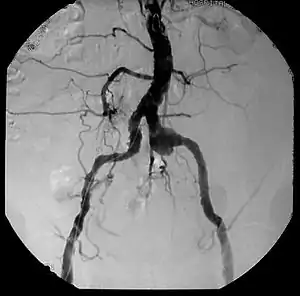

![]() | |

| Aneurysm, a commonly lethal complication of SA | |